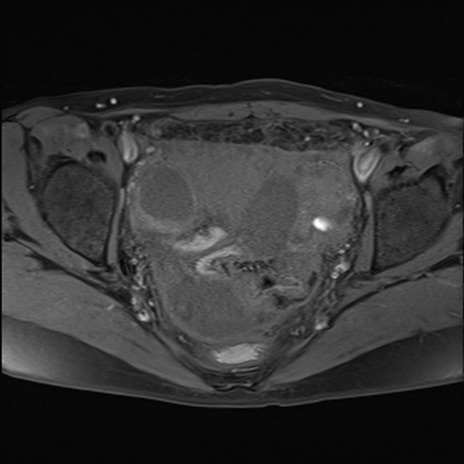

症例39 脂肪抑制T1WI(横断像)

MRI(4日後)

T1WI(横断像)